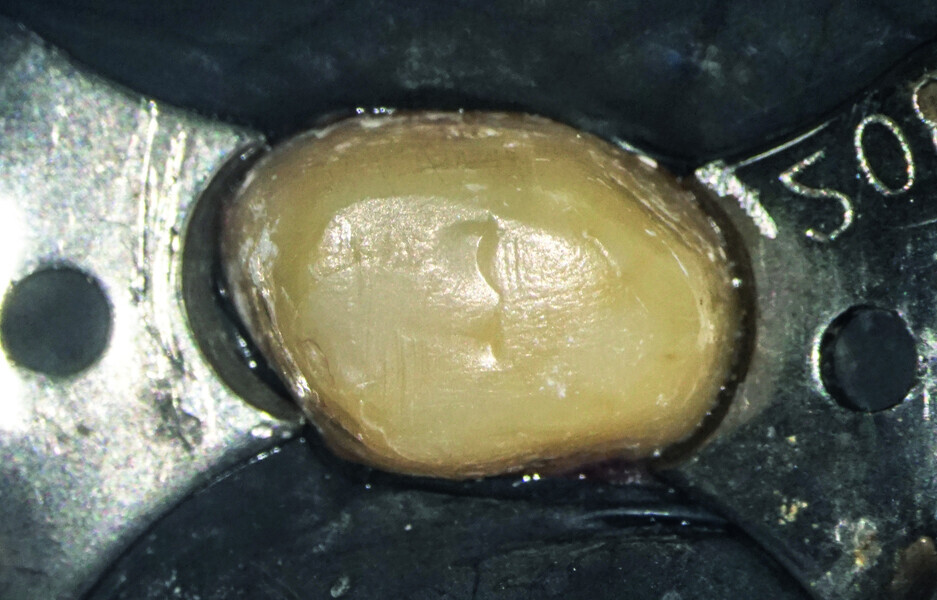

Minimally invasive root canal shaping—A new protocol